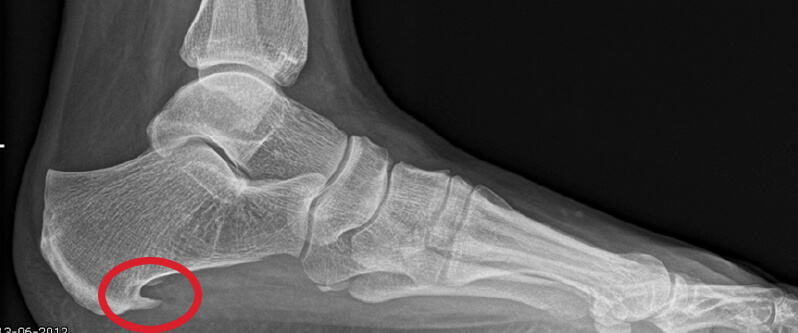

Hielspoor duidelijk zichtbaar op deze op röntgenfoto.

Een hielspoor is een botuitwas (verkalking) aan de onderzijde van het hielbot, het zogenoemde calcaneus. Deze verkalking bevindt zich op de plaats waar de peesplaat onder de voet, de fascia plantaris, aanhecht. Een hielspoor is goed zichtbaar op röntgenfoto’s en kan ook met echografisch onderzoek worden vastgesteld.

Een röntgenfoto kan een hielspoor zichtbaar maken, maar is niet altijd noodzakelijk. Met echografie kan de dikte en kwaliteit van de fascia plantaris worden beoordeeld en kan worden vastgesteld of er sprake is van overbelasting of degeneratie.